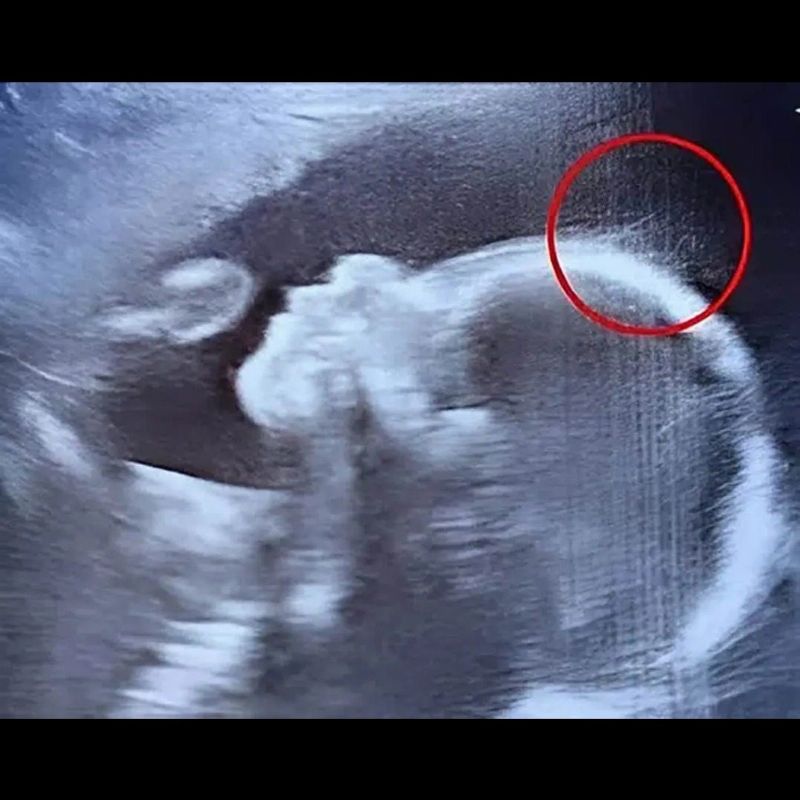

Os médicos ficaram chocados durante o ultrassom: a história dessa bebê vai te surpreender

Emily, aos 29 anos, aguardava ansiosamente o momento de ouvir o batimento cardíaco de sua bebê durante um ultrassom de rotina.